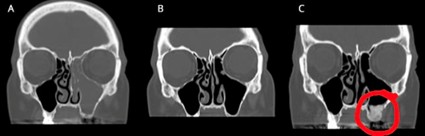

Na imagem acima vemos em (a) os seios maxilar e etmoidal esquerdos acometidos por doença (cinza). Em (b) é possível ver os seios maxilar e etmoidal preenchidos por ar (preto), já após a abordagem cirúrgica nasal e em (c) é visível a correção da abertura (círculo vermelho).

Na imagem acima, de tomografia dos seios da face, temos uma visão de frente onde o preto é ar, o branco é osso e o cinza é tecido mole ou secreção. Na imagem é visível uma fratura dentária (círculo vermelho) com uma comunicação do seio maxilar direito com a cavidade oral, o que gera uma obstrução do seio e acúmulo de secreção no seio maxilar e no seio etmoidal direitos (setas azuis).